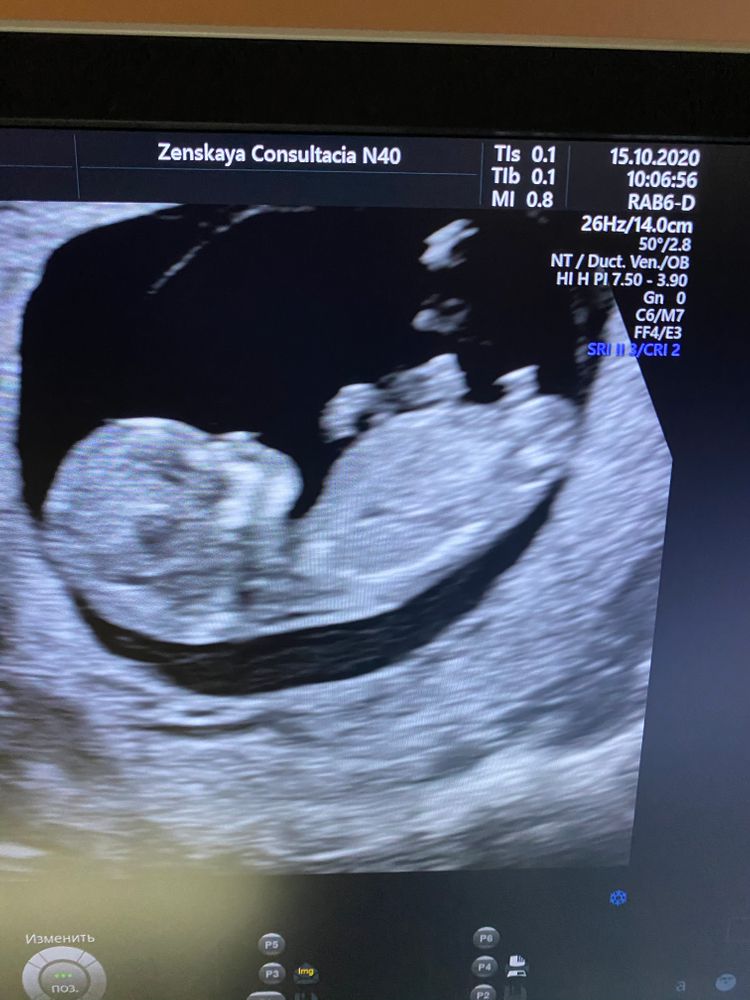

Первый скрининг 11 недель 3 дня

Сегодня сходила на первый скрининг , ужасно волновалась

Сказали , что все хорошо , кровь тоже сдала

Вот думаю насчёт пола , сказали , что 70-80%, что мальчик